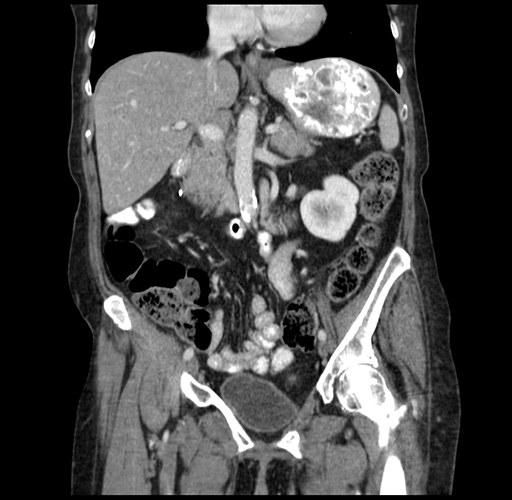

Pre-Chemo: Coronal Venous

Coronal Venous